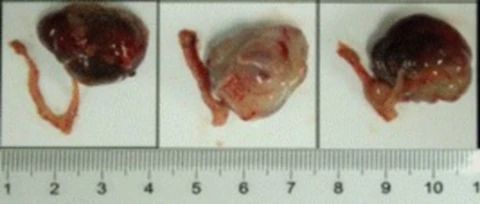

²¿·ÖÃÀ¸ß÷PDXÔλģ×Óչʾ